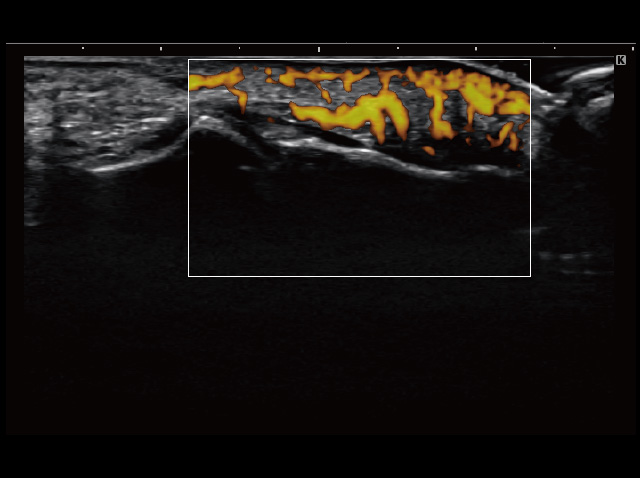

| モード | B、M、Color、Power、SCF、PW、CW*1、TDI、 ストレインエラストグラフィ*2 |

イメージギャラリー

イメージ画像を表示する